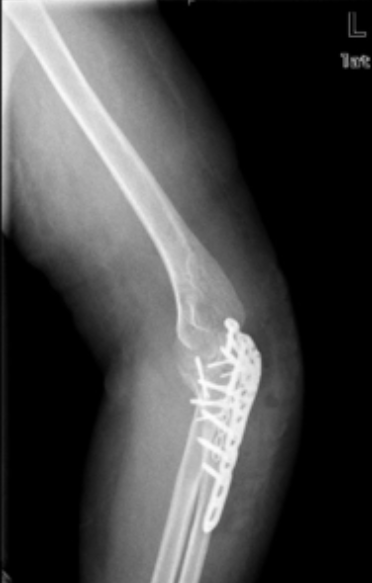

临床诊断冠状突骨折时常采用CT、X线片以及三维重建这三种影像学检查。

CT检查冠状突骨折时能够清晰地辨别出骨折的位置、骨折粉碎的程度以及骨折线的走向等,但是在直观性与整体性方面有所欠缺。

X线片检查冠状突骨折时相较于CT检查,其整体性与方便性较高,检查人员能够直观的看到患者冠状突骨折以及周围组织损伤的情况,方便医生作进一步的诊断。但是X线检查仍存在一些不足,当冠状突的体积较小时,如果有重叠遮挡的情况,通过X线很容易发生漏诊的情况;如果患者冠状突骨折伴有其他肘关节组织损伤,X线不容易辨别骨折块的来源;X线无法实现全方位观察关节面,使得检查人员能够观察的角度受限。

与CT检查和X线检查相比,三维重建在检查冠状突骨折时具有较好的优势,它不仅能够直观的看到骨折特征,还能从不同的角度来观察骨折的形态,提高了医生对冠状突骨折的分型、诊断与评估的准确性。